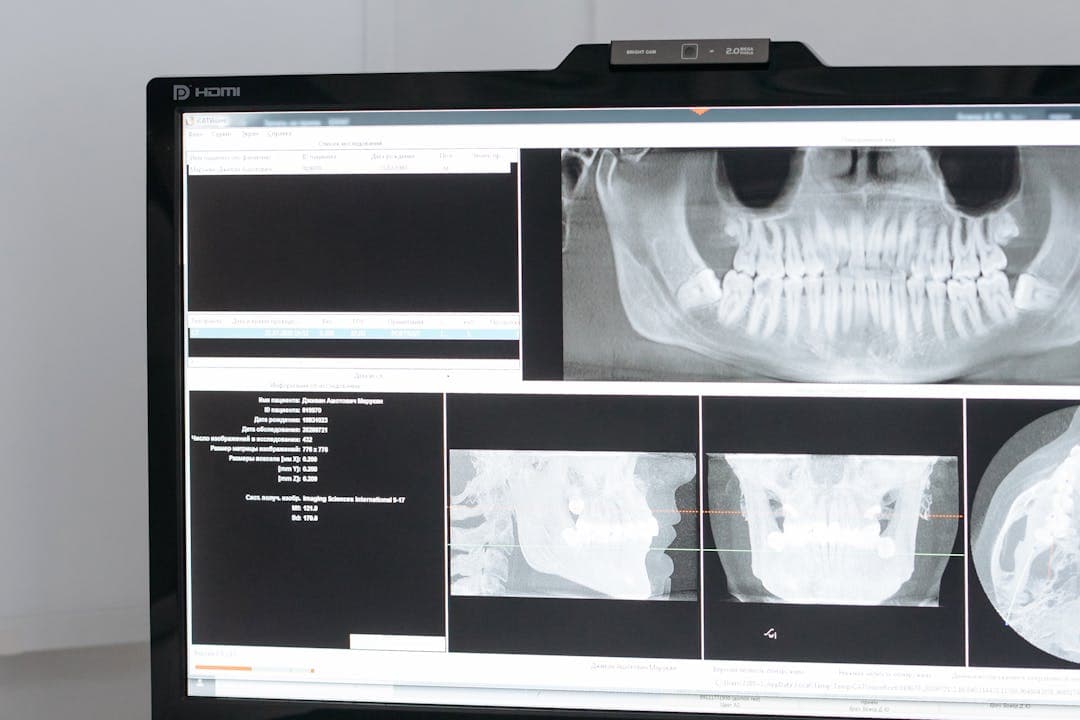

- 3D CT와 파노라마 엑스레이로 잇몸뼈·신경·염증 상태 확인

- 신경·턱뼈 위치에 맞춰 3D 수술 가이드 설계

- 1mm 오차도 줄이는 정밀 임플란트 시술의 핵심 도구입니다

📊 CT로 확인되는 뼈 상태

| 뼈 두께 | 임플란트 가능 여부 |

| 6mm 이상 | 뼈이식 없이 가능 |

| 4~6mm | 소량 뼈이식 병행 |

| 4mm 이하 | 고난도 뼈이식 필요 |

📌 2. 진단 장비의 유무

- 3D CT, 파노라마, 모의 수술 기능이 있어야 정밀한 임플란트가 가능합니다.